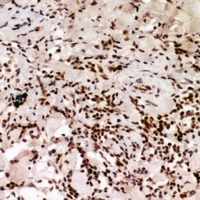

IHC (Immunohiostchemistry)

(Immunohistochemical analysis of HP1 alpha (pS92) staining in human breast cancer formalin fixed paraffin embedded tissue section. The section was pre-treated using heat mediated antigen retrieval with sodium citrate buffer (pH 6.0). The section was then incubated with the antibody at room temperature and detected using an HRP conjugated compact polymer system. DAB was used as the chromogen. The section was then counterstained with haematoxylin and mounted with DPX.)